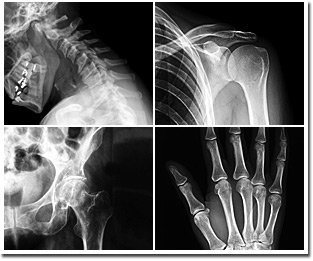

Il servizio prevede visita specialistica e valutazione medica, il trattamento di patologie muscolari ed articolari, infiltrazioni endoarticolari, ecografie muscolo-tendinee, ecografie delle anche.